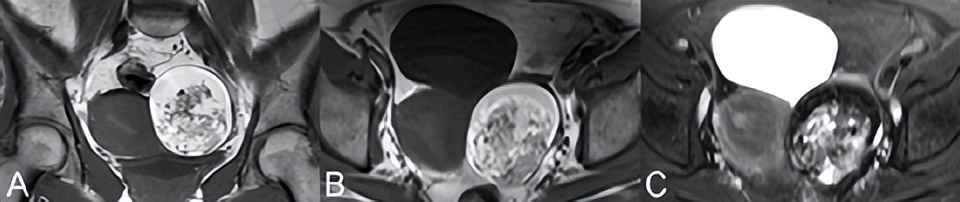

畸胎瘤可能含有囊性成分。皮样囊肿(即成熟囊性畸胎瘤)通常含有分泌脂肪皮脂腺物质的突出外胚层。通常会出现含有脂肪、毛发、骨骼或牙齿的实心非增强性突起(即Rokitansky)。图76.3中的(A)冠状位和(B)轴位T1WI显示了一个不均匀出现的囊性肿块,具有明显的高信号成分。这种高信号可见于出血性囊肿和子宫内膜异位,但(C)脂肪抑制T2WI上的信号丢失证实了皮样囊肿的存在。STIR抑制脂肪是非特异性的(即所有T1短的质子都被抑制),不能进行上述区分。微小脂肪含量可能无法通过频率饱和检测到

可通过同反相位GRE T1WI上的信号减低更好地识别。增强,实性成分有利于恶性肿瘤诊断,比如未成熟的畸胎瘤。皮样囊肿易导致卵巢扭转,最初表现为基质水肿样信号,但由于坏死和出血,信号随时间变化。CE T1WI无增强是卵巢梗死的特异性表现,但考虑到卵巢的双重血供,对扭转不敏感。其他发现包括同侧子宫偏斜、腹水和卵巢血管充血。

▲ 图76.3